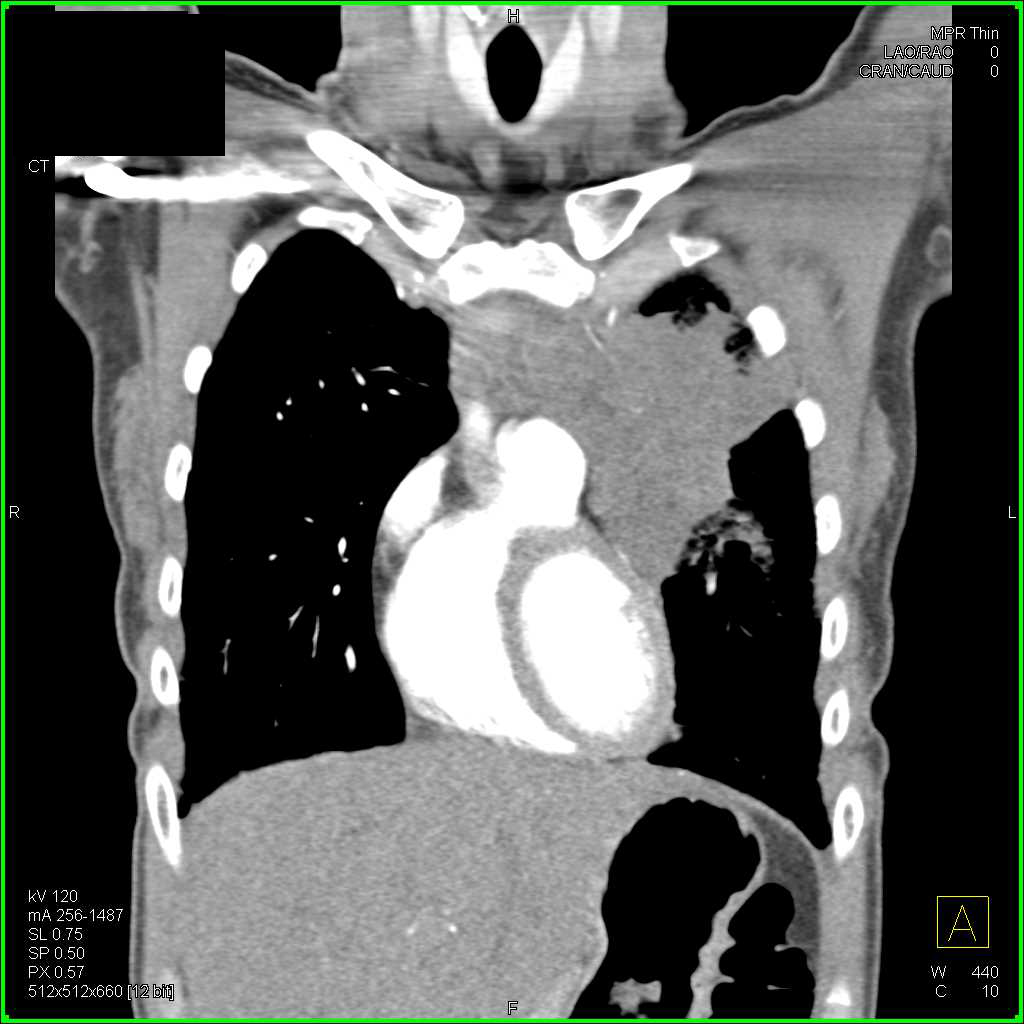

From www.ctisus.com

Lymphoma on Chest Xray X Rays Case Studies CTisus CT Scanning Chest X Ray For Lymphoma The amount of radiation used in most diagnostic tests is so small that it poses little risk to the patient. To look for possible signs of lymphoma coming back after treatment; Findings on a chest x. To look for possible signs of cancer coming. The primary investigation of suspected lung and mediastinal pathology is standard chest radiography. However, nccn imaging. Chest X Ray For Lymphoma.

From ctisus.com

Lymphoma with Mediastinal, Lung Parenchymal and Renal Involvement Chest X Ray For Lymphoma However, nccn imaging guidelines for lymphoma surveillance state that it is acceptable to perform chest radiography or ct of the chest every six to 12 months for the. To look for possible signs of lymphoma coming back after treatment; The amount of radiation used in most diagnostic tests is so small that it poses little risk to the patient. To. Chest X Ray For Lymphoma.

Lymphoma Involves the Chest Wall Chest Case Studies CTisus CT Scanning Chest X Ray For Lymphoma However, nccn imaging guidelines for lymphoma surveillance state that it is acceptable to perform chest radiography or ct of the chest every six to 12 months for the. To look for possible signs of lymphoma coming back after treatment; Lymphomas are classified according to the who classification of tumors of hematopoietic and lymphoid tissues based on cell of origin (e.g.. Chest X Ray For Lymphoma.